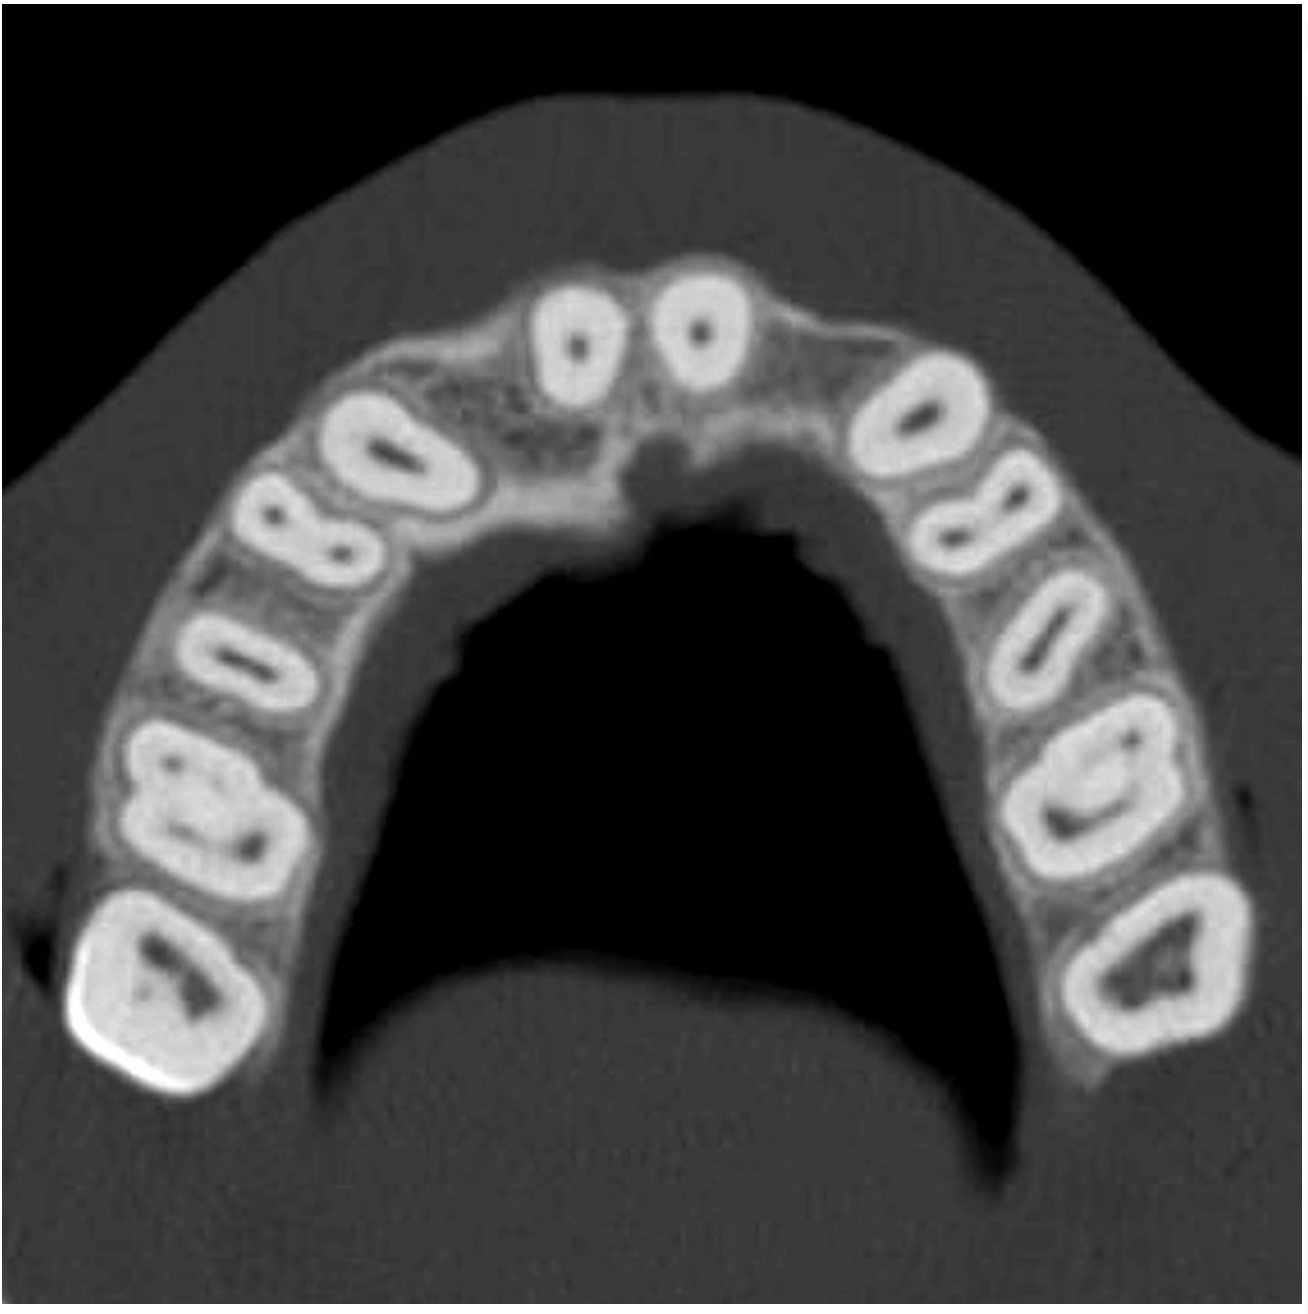

The CT axial views represent an important instrument in gaining a better understanding of anatomical features that can not be determined by any other imaging modality (Figure 6A). When the maxilla is sliced axially at the level where the roots meet the crest of the bone, the adjacent and surrounding root morphology can be revealed. Of note are the individual and different shapes of each of the central incisors, canines, premolars, and molar roots. These images reflect a phenomenon defined by the author as the “restorative dilemma.” Clinicians encounter this often difficult dilemma when attempting to re-establish morphologically correct emergence profiles in prosthetic teeth as they ascend from the round shape of the implant(s). When planning for the placement of the implant in the left lateral incisor area, there appeared to be adequate mesial-distal space between roots as seen in the axial view of Figure 6B. A closer inspection of the planned site for the right lateral incisor revealed a more narrow space, further.complicated by the distal rotation of the palatal aspect of the tooth root. Based on this preliminary position, the 3.75-mm diameter, straight-walled implant can be seen encroaching on the lamina dura periodontal ligament space of the right canine and central incisor. If there was not adequate room for this diameter and type of implant, the adjacent teeth could sustain potential iatrogenic damage. Therefore, additional “tweaking” of the virtual placement was necessary to diminish this risk.

Figure 6a  By slicing the maxilla axially, the images revealed (A) the differing morphology of the central incisors, canines, premolar, and molar roots, and (B) the left simulated implant seen encroaching on the adjacent lamina dura.

Figure 6a

Figure 6b  By slicing the maxilla axially, the images revealed (A) the differing morphology of the central incisors, canines, premolar, and molar roots, and (B) the left simulated implant seen encroaching on the adjacent lamina dura.

Figure 6b